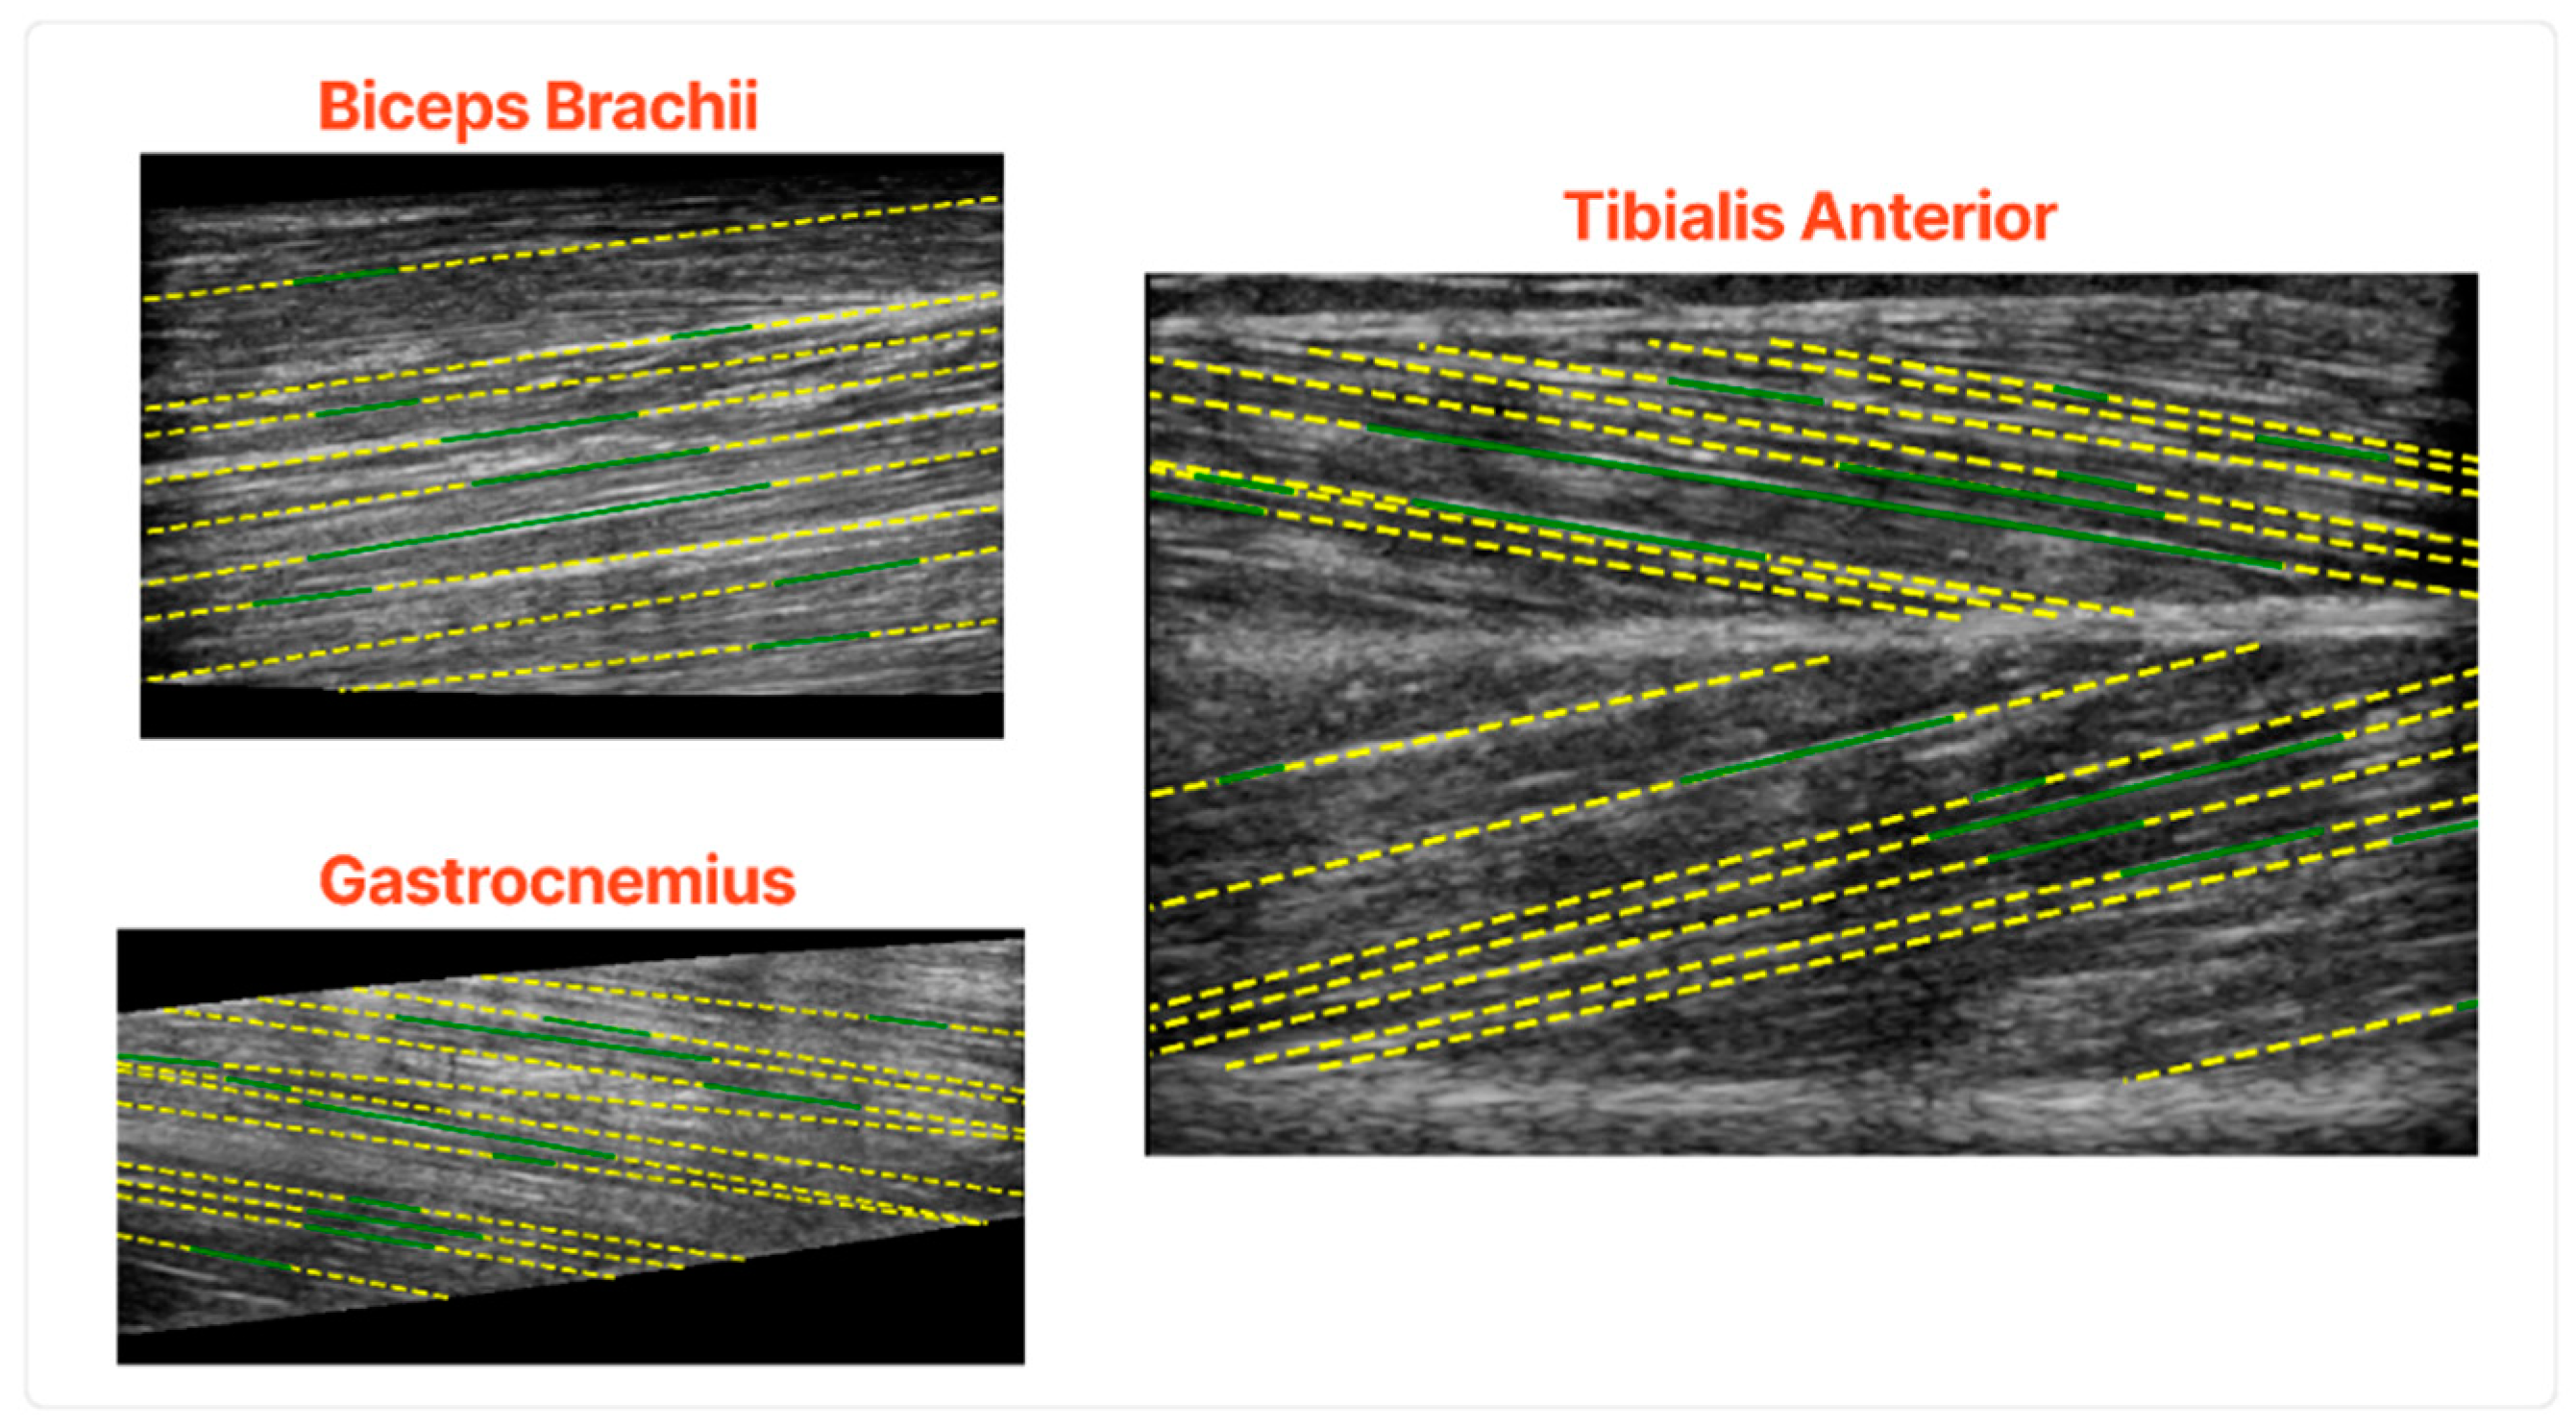

- The longitudinal ultrasound scans of the Biceps Brachii (BB) muscle at two-thirds of the distance from the acromion to the elbow crease;

- The longitudinal ultrasound scans of the bulkiest part of the medial head of the Gastrocnemius (GCM) muscle;

- The longitudinal ultrasound scans of the Tibialis Anterior (TA) muscle at one-quarter of the distance from the inferior pole of the patella to the malleolus lateralis.

2.3.1. Muscle Fascicles Extraction

- Firstly, for the case of BB muscle, the initial image needs to be horizontally flipped to smoothly apply the procedure mentioned above;

- Secondly, in the case of TA, the two muscle compartments depicted in Figure 1 as (c1) and (c2) have to be isolated (c2 must also be flipped horizontally) to be able to detect the fascicles;